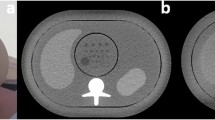

Comparison of CT images acquired with the reference protocol and two protocols that yielded superior detectability results. a Reference protocol (120 kVp, TCM SD of 7.5, pitch of 0.813, AIDR 3D). b Reduced tube voltage and tube current (100 kVp, TCM SD of 10, pitch of 0.813, AIDR 3D). c Reduced tube voltage and increased pitch (100 kVp, TCM of 7.5, pitch of 1.388, AIDR 3D). The drawing indicates the lesion position, and lesions are additionally indicated by white arrows in the CT images. Images are displayed with window level/window width 40/350 at 120 kVp and 80/350 at 100 kVp

Figure 4 presents the results of the non-inferiority analysis. Compared with the reference protocol, seven protocols yielded non-inferior detectability at a reduced dose and thus improved protocol performance (Table 1). The strongest dose reduction at non-inferior detectability was achieved by reducing tube voltage to 100 kVp and increasing the TCM noise level to SD 14 (AUC 0.865, 95% CI: 0.824 to 0.905; DLP 5.1 mGy•cm). Two protocols reduced dose and yielded superior detection results, which means that dose exposure and image quality were improved simultaneously. One of these protocols used a lower tube voltage of 100 kVp and a higher pitch of 1.388, which increased the AUC to 0.891 (95% CI: 0.842 to 0.939) and reduced the DLP to 13.4 mGy•cm. The other protocol used a lower tube voltage of 100 kVp and higher TCM noise level of 10, which increased the AUC to 0.884 (95% CI: 0.844 to 0.924) and reduced the DLP even further to 7.3 mGy•cm. For comparison, Fig. 5 presents CT images acquired with these two protocols and the reference protocol.